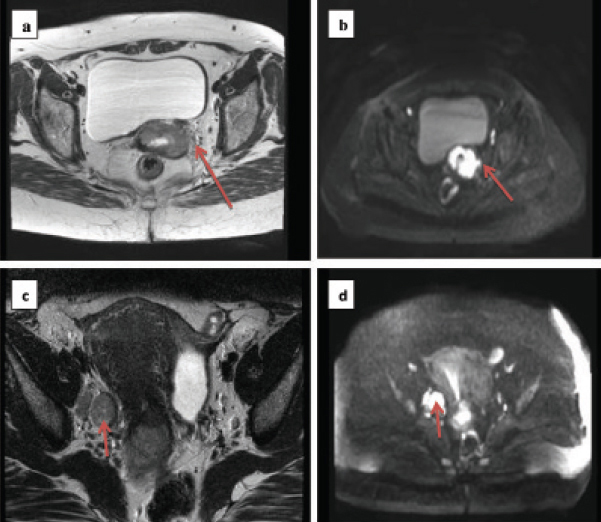

Cervical cancer is an important public health problem characterized by high mortality to incidence ratio in developing countries like India. Inspite of advancement in diagnosis and therapy, survival in locally advanced cervical cancer is still dismal [26]. Though concurrent chemoradiation is the standard of care, benefit of addition of chemotherapy is debated especially in locally advanced settings [27]. Updated Cochrane meta-analyses [28] showed that benefit of addition of concurrent chemotherapy to radiotherapy, particularly in stages III-IVA, is minimal (3%). A large proportion of patients in developing countries present in locally advanced stages. Therefore, in the present scenario, prognostication of the disease with non-invasive imaging biomarker is highly relevant translational research. This will help to choose patients for intensification of therapy. Traditionally, clinical examination remains gold standard for evaluation, but MRI is emerging as an important adjunct in diagnosis and management of carcinoma cervix [29], both in early and locally advanced cases [30]. The role of volumetric and functional parameters of MRI, is an active area of research in staging, prognostication, management and follow up [31]. Conventional T2HR MRI along with DWI is useful adjunct in delineating not only the tumour but also the disease extension to lower uterine segment, parametrial involvement [Table/Fig-6,7a,b], vaginal involvement, nodal involvement [Table/Fig-7c,d], involvement of adjacent structures [Table/Fig-8a,b] and differentiating metastatic lesions from benign lesions [Table/Fig-9a,b]. DWI provides a good depiction of the primary tumour, residual disease and helps in assessing response after treatment [29]. This has significant implication not only in diagnosis but also in deciding the optimal therapy in multidisciplinary tumour board.

a) T2 weighted image showing cervical tumour with left sided parametrial stranding not appreciated in clinical examination; b) Diffusion weighted image showing restricted diffusion in the same region; c) T2 weighted image showing tumour with large right sided obturator node; d) Diffusion weighted image showing restricted diffusion in the nodal region.